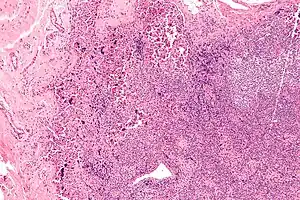

| Lymphadenopathy due to systemic lupus erythematosus with characteristic necrosis and haematoxylin bodies. H&E stain. | |

Generalized lymphadenopathy is swollen lymph glands in many areas of the body.[1]